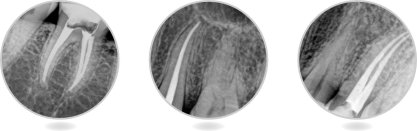

1.用充填筆封密根尖孔:

![]()

步驟1A用根管銼將根管備成所需的形狀,檢查根管長度,選擇適合的主尖,充填在根管內(nèi)部。

步驟1B把充填筆頭放置在根管內(nèi)部4—7MM處,然后在合適的位置放上帶顏色的標(biāo)識(shí)膠墊。

步驟2將蘸有根管封密劑的主尖填入根管內(nèi)。

步驟3A把充填頭放入根管孔內(nèi),按住開關(guān)按鈕加熱,切斷GP中間部位,然后將充填頭壓至距根尖孔6-9mm處,壓1.5-2秒鐘。

步驟3B松開按鈕,使充填頭冷卻,同時(shí)繼續(xù)推動(dòng)充填頭并保持8秒鐘對(duì)根尖的擠壓,使根尖得到完全的充填。然后按住操作鈕1-1.5秒,再次開啟DIA-PEN,將牙膠尖充填到距根尖孔4-7mm處。

步驟4使用充填器將剩余的充填料壓緊。